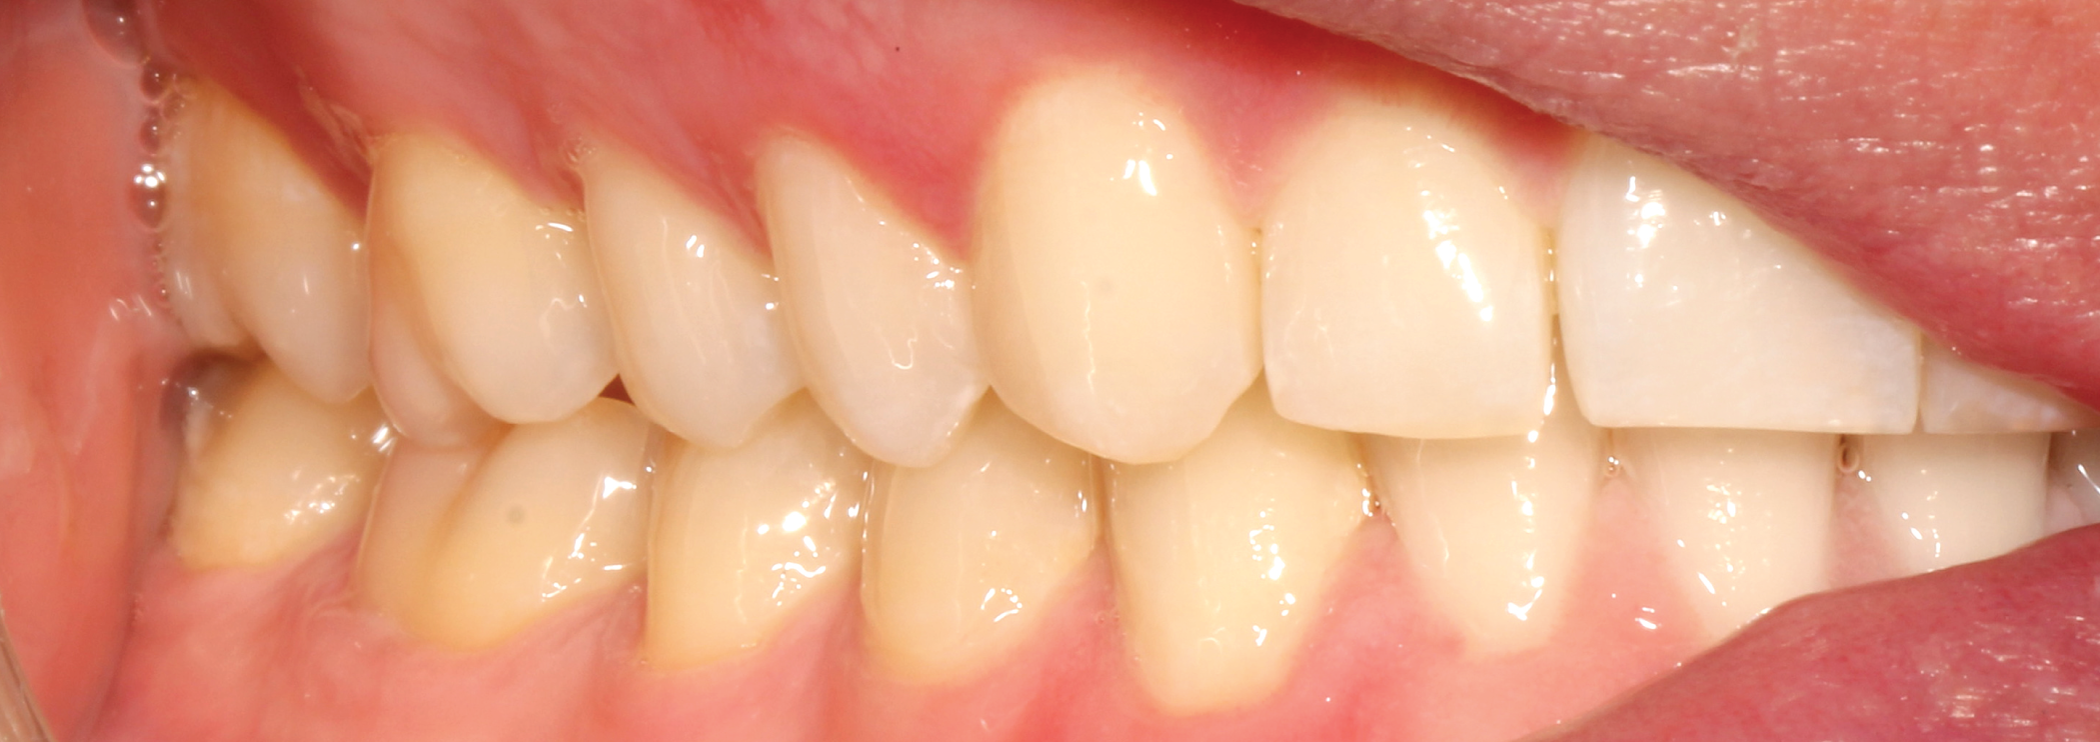

Fig. 7: Pre-op (right lateral view) Fig. 8: Pre-op (left lateral view)